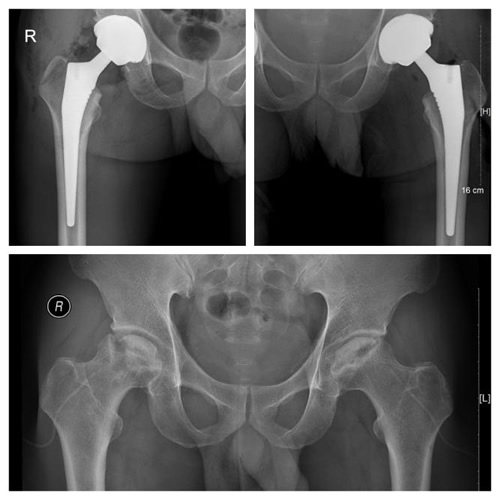

由于关节置换手术中需要进行截骨、磨锉、打入假体等一系列复杂操作,手术医师容易受到溅血污染,风险远较一般手术大。有了第一次手术的经验,参与手术的医护与麻醉人员在术前从容地准备了各种措施。术前使用氨甲环酸等止血药物辅以术中控制性降压来减少出血,术中使用一次性的防水铺巾、手术衣及防护面罩,对可能污染的位置着重进行严密防护。在手术护士与麻醉医生的精心配合下,手术历时1小时,术中出血不到100ml,张文明与李文波两位主任便完成了这台普通而不简单的手术。术后所有的器械均送至我院供应室做特殊消毒处理。第二天,林先生即下地行走,感觉疼痛得到明显缓解,摄片显示,髋关节假体的位置很理想,患者对手术效果非常满意。

术后患者髋关节假体的位置理想